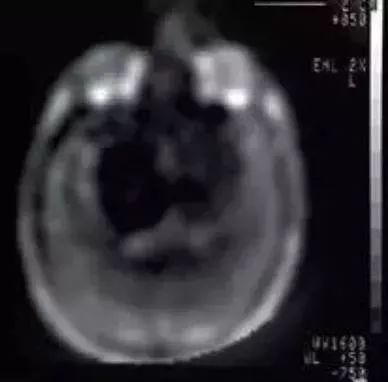

在美国,纽约大学的雷蒙德·达马迪安教授团队则在医学成像方面,拔得头筹,他们研制的医用核磁共振设备(图7)于1977年7月3日到了第一幅人体磁共振图像——胸部轴位质子密度加权图像(图8),标志着MRI技术在医学领域应用的开始,因此7月3日也被学界认为是医学磁共振成像技术的“生日”。

图8 第一幅人体磁共振图像